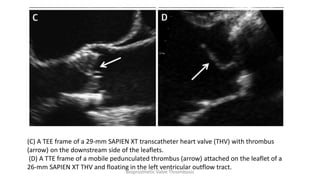

(C) A TEE frame of a 29-mm SAPIEN XT transcatheter heart valve (THV) with thrombus

(arrow) on the downstream side of the leaflets.

(D) A TTE frame of a mobile pedunculated thrombus (arrow) attached on the leaflet of a

26-mm SAPIEN XT THV and floating in the left ventricular outflow tract.